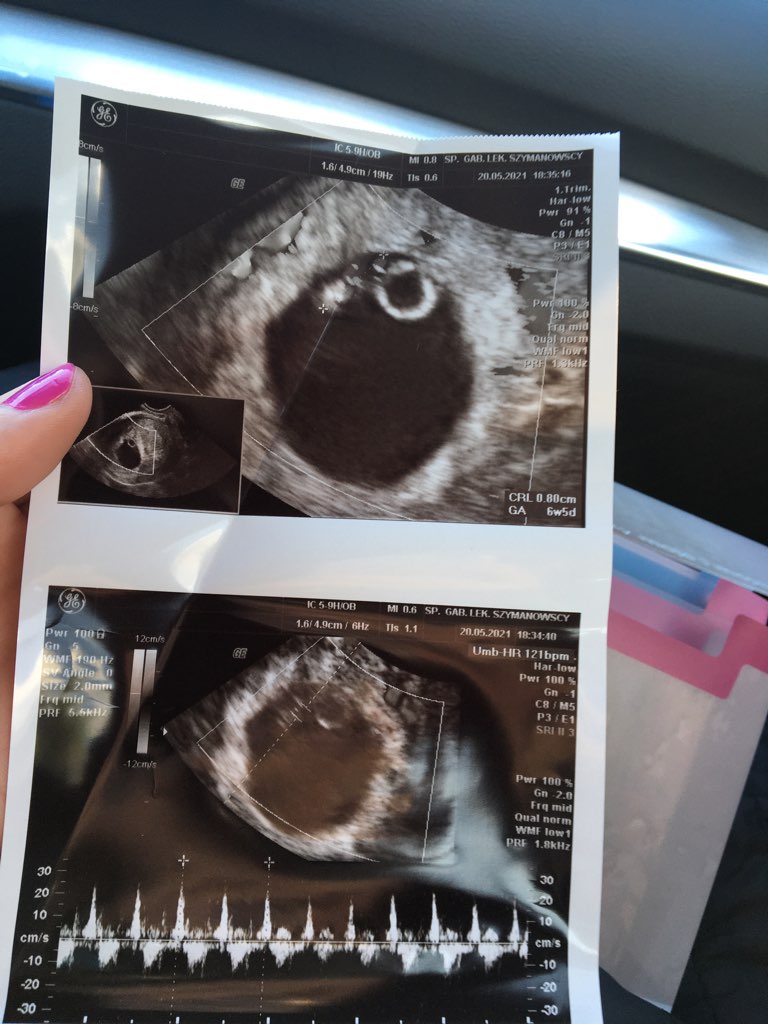

Serduszko 121 uderzeń 😍 termin mi się zmienił na 8.01.22 ale zmienić się może nieraz jeszcze. Tak delikatnego doktora nigdy nie widziałam.